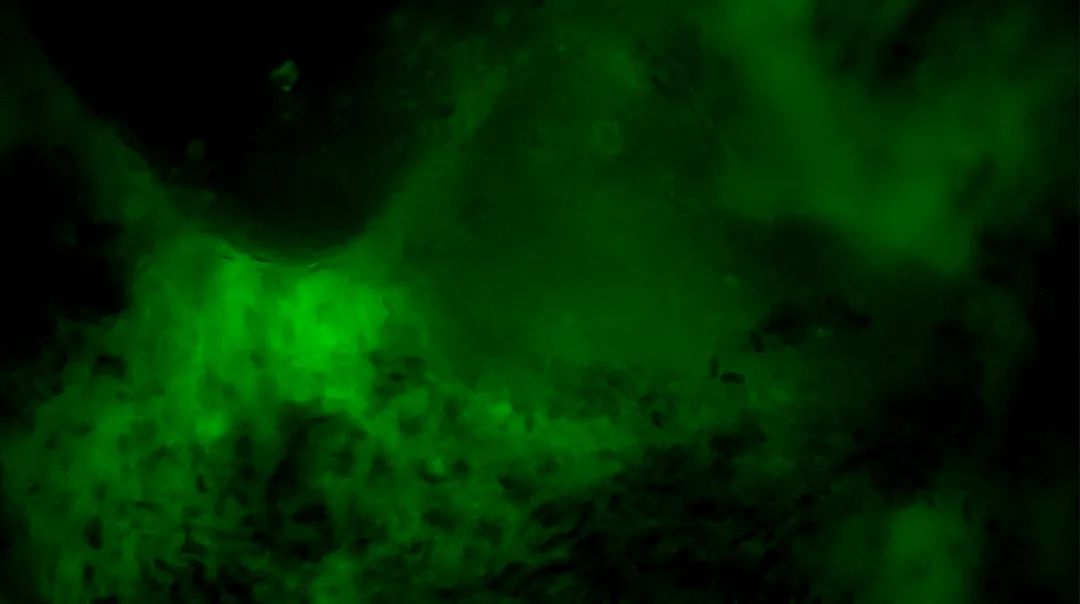

3次切緣掃查的EndoSCell?細(xì)胞圖像

1

陽性,細(xì)胞核異型、密集、分布不均勻

齊魯醫(yī)院開啟精準(zhǔn)手術(shù)新篇章,細(xì)胞級熒光導(dǎo)引技術(shù)助力腦膠質(zhì)瘤最大化安全切除(圖5)

2

齊魯醫(yī)院開啟精準(zhǔn)手術(shù)新篇章,細(xì)胞級熒光導(dǎo)引技術(shù)助力腦膠質(zhì)瘤最大化安全切除(圖6)

3

陰性,細(xì)胞核形態(tài)正常、分布均勻

齊魯醫(yī)院開啟精準(zhǔn)手術(shù)新篇章,細(xì)胞級熒光導(dǎo)引技術(shù)助力腦膠質(zhì)瘤最大化安全切除(圖7)